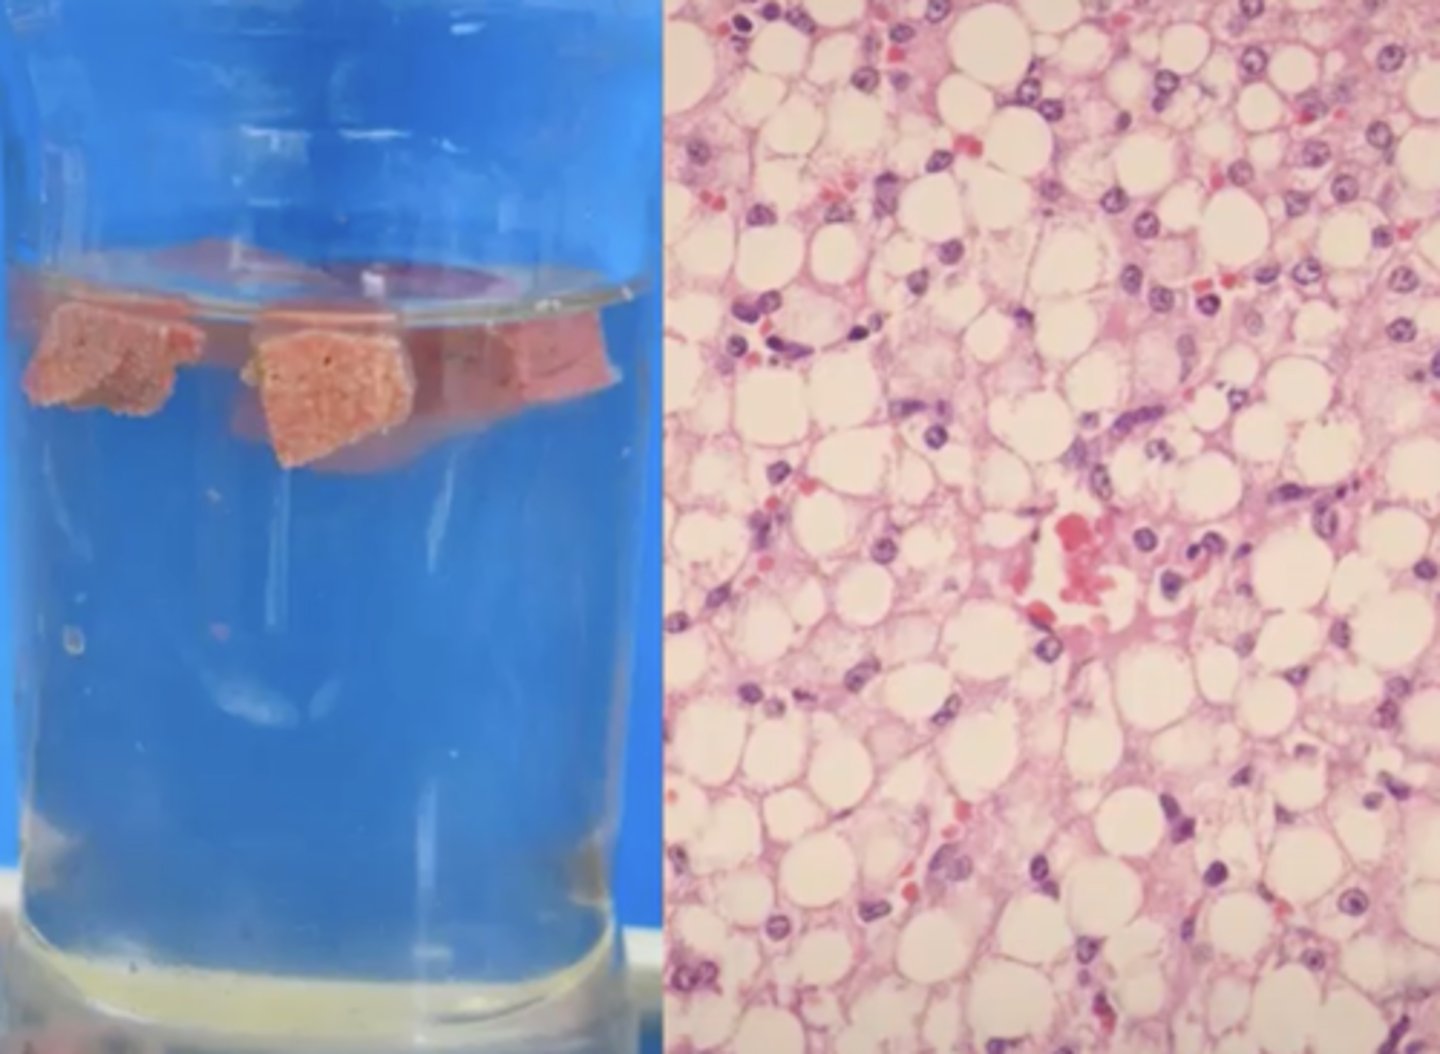

Hepatic lipidosis - glycogen caused

-very common

-notice the sinusoids are pushed out of the way in the histopath image

-can see in starvation cases + obesity

What has caused this gross and histologic lesions?

Hepatic lipidosis

Cat liver: What is wrong here?